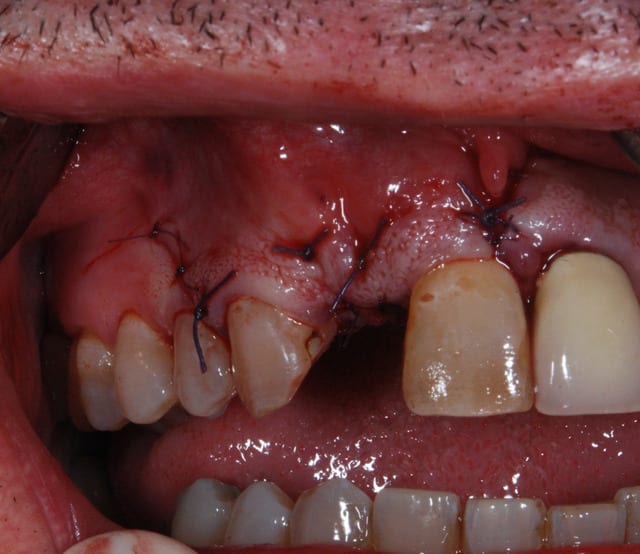

pas que pour le granulome...d'ailleurs...mais aussi parce que tu as une belle fracture vestibulaire qui fait que la corticale...bein y en a plus...ou quasi plus...

la seule condition pour tenter: faire une box technique au sonicweld...et encore, autant dans un secteur pas trop esthétique, je dis pas...mais là...si çà foire c'est le drame...

beau travail, mais

les 2 cas ne me semblent pas comparable dans la mesure ou tu as réussi à préserver un bandeau d'os vestibulaire presque au niveau des collets. Il permet un effet piquet de tente incomparable et évite les mauvaises surprises de perte importante de volume de biomat a la cicatrisation.

Dans l'autre cas la table vestibulaire est manquante, le résultat d'une EII beaucoup moins prévisible et dans un secteur esthétique j'aime pas jouer a la roulette russe.

Moi ce qui me choque , c est de greffer "en milieu infecté".